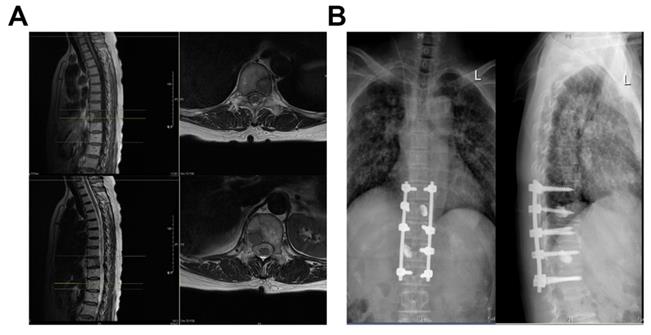

Surgical treatment options were divided into excisional and palliative surgery. Excisional procedures include total en-bloc discectomy (TES) and intralesional excision (Case Figure 1), for example, segmental discectomy in patients with thoracolumbar metastases in a single vertebra or 2 consecutive vertebrae with an overall revised Tokuhashi score of 7-11. Palliative surgeries included: decompressive laminectomy and posterior pedicle screw insertion, mainly for patients with a revised Tokuhashi score of 0-8. The surgery was performed by experienced orthopedic surgeons from Zhongshan Hospital, Fudan University.

Figure 1

Case: Female, 60 years old, thoracic vertebrae 10 and 12 with lung cancer metastases. (A) Preoperative MRI; (B) Three Months Postoperative X-Ray.